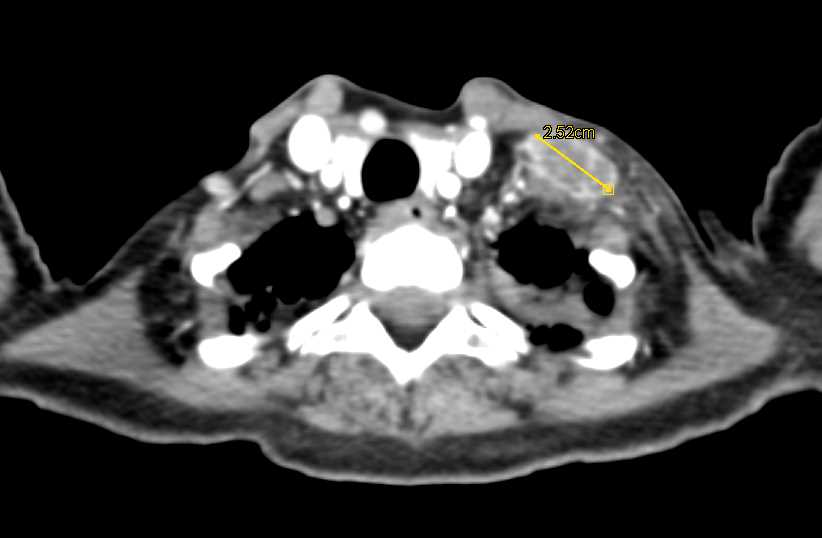

Diagnosis

Incidental Bladder Cancer in Patient with Prior Whipple Procedure